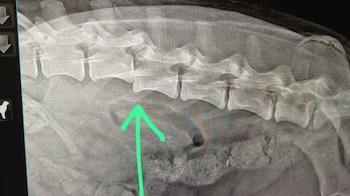

La evaluación determinó una vértebra desprendida, aunque sin daño medular. El diagnóstico proporcionó una perspectiva optimista respecto a la recuperación de Akira, ya que “no perdió sensibilidad”, según explicó Malaspina a LM Neuquén.

Al describir el procedimiento necesario, la proteccionista señaló que se debe colocar una placa para estabilizar la columna y así darle la posibilidad de caminar otra vez.